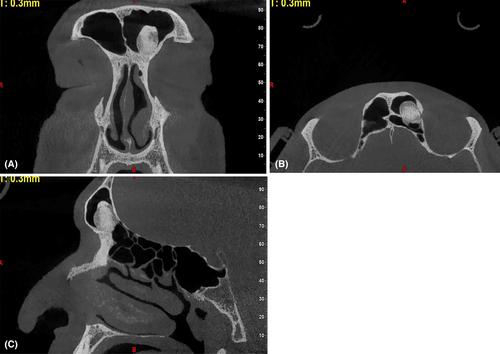

骨瘤是最常见的间质肿瘤。认识其放射学特征对于早期诊断、及时治疗和患者随访、预防并发症至关重要。本病例报告描述了一位在不相关的影像学检查中偶然发现额窦骨瘤的患者。

Osteoma is the most common mesenchymal tumor. Recognizing their characteristic radiographic features is crucial for early diagnosis, prompt treatment, and patient follow-up, preventing complications. This case report describes a patient with an incidentally detected osteoma of the frontal sinus found during unrelated imaging examinations.